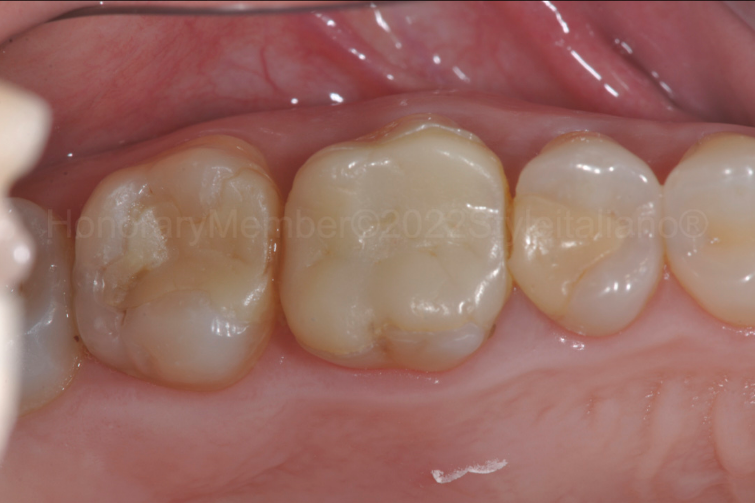

图七:为了给嵌体修复提供所需的厚度,进行了嵌体修复的预备。深的龈壁边缘不再存在。由于牙本质替代物,我们将龈壁边缘提高到龈上水平,以精确所有即将到来的临床步骤(印模、临时和粘接方案)。